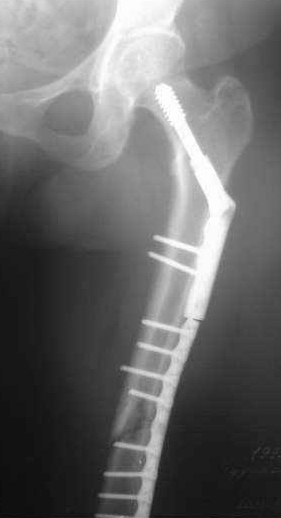

Сегодня мною была осмотрена больная, которой я выполнил накостный остеосинтез около четырех месяцев назад по поводу фрагментарного перелома бедра на уровне средней трети и межвертельной зоны.

Перелом синтезированный DHS сросся, а вот на уровне средней трети - нет. И, похоже, есть нехорошая тенденция к резорбции.

Больную беспокоит умеренный отек голени и стопы. Нагрузку на конечность не разрешаю, ибо недавно у молодого пациента при аналогичном переломе и остеосинтезе произошел перелом пластины на уровне нижней трети бедра...

По поводу моей больной с фрагментарным переломом бедра ...

Больная 47 лет, поступила в отделение после автодорожной травмы от 08 июля сего года с DS: ЗЧМТ, СГМ. Закр. чрезвертельный перелом и перелом с/3 левого бедра со смещением. Ушиб и рваная рана левого коленного сустава. Соп.: Хр. железодефицитная анемия. (Гемоглобин при поступлении 71 г/л). 08 июля - ПХО ран колена.

11 июля остеосинтез бедра DHS + LC DCP.

Я выкладывал на Форум этот случай, где высказывались опасения, что не исключается варусная дислокация межвертельного перелома на фиксаторе из-за малой длины Screw ... вроде пронесло ... перелом сросся. Но маленькая

победа в отдельной битве, все же не принесла победы в целом... Остается неопорная конечность, ограничение движений в коленном суставе 180 - 150 град., отечность голени и стопы, по-видимому, из-за сосудистой недостаточности, гипотрофии

мышц ноги ... При выписке из стационара Hb - 97 г/л (препараты железа, рибофлавины).

По настоящий момент наблюдается амбулаторно. Передвигается с опорой на костыли. Горит желанием встать "на крыло" ... Ждем Вашего решения. Может быть нужны дополнительные снимки?

Возьметесь ли за этот случай? Ну, и самое главное - стоимость лечения ...